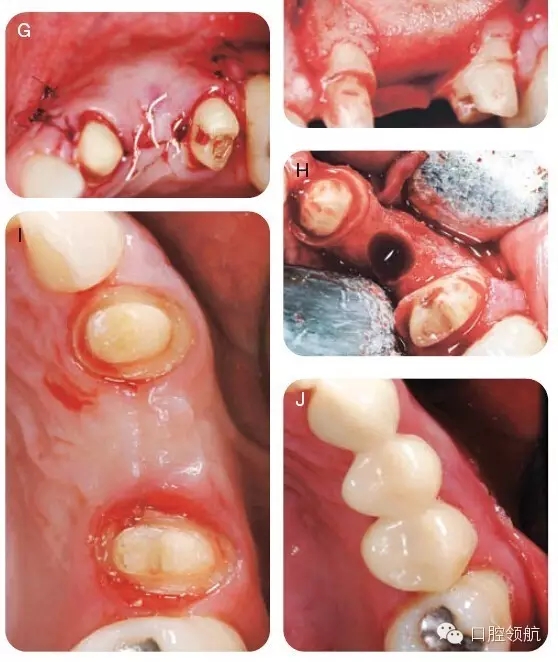

用2%利多卡因(1/100000腎上腺素)行下牙槽后、中神經(jīng),腭大神經(jīng)阻滯麻醉,局部浸潤麻醉。附加兩個垂直方向的松弛切口使得視野更加清晰并減低術后瓣撕裂的可能,上頜右側1/4區(qū)域翻開全厚瓣以充分暴露骨皮質(圖6A~C)。暴露術區(qū),用圓形金剛鉆去除該區(qū)的骨皮質,使得術區(qū)有血液流出。打入兩個10mm的支帳螺絲并且確認其穩(wěn)定(圖6D)。取稍過量的脫礦凍干骨置于該區(qū)域(圖6E)。放置堅固的可吸收膠原膜( O s s e o g u a r d -Collagen Matrix, Inc, Franklin Lakes,NJ, USA)于移植物上(圖6F),復位瓣并原位縫合。組織愈合良好(圖6G)。在GBR術后6個月,再次麻醉并暴露術區(qū),制備直徑為4.1mm的植入位點,使得頰舌側有足夠的余留骨,以確保組織的長期穩(wěn)定性并防止組織退縮(圖6H),在最終固定冠修復前,拍攝照片,顯示牙槽骨寬度顯著改善(圖6I,J),圖7為最終修復當日照片。

圖6 (A~J)手術時的口內照。